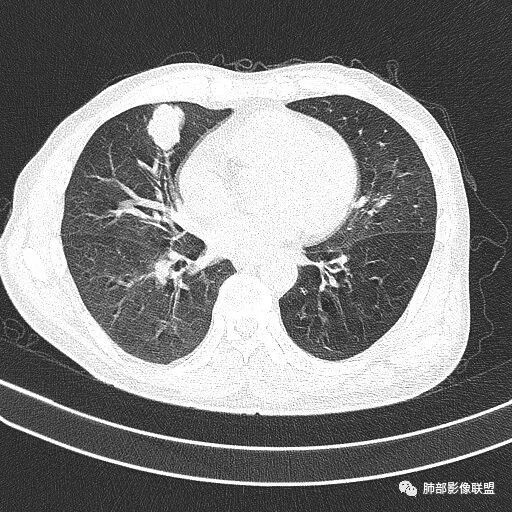

实性还是GGO?      实性

边界清楚、光滑?     光滑清楚,浅分叶,无明显毛刺

与支气管关系如何?   能看清楚吗

如果这时候我建议补充下面的层面,最好薄层

看起来堵了

南边:

按这个就是堵了

我们一般是找肺动脉,伴行支气管

堵了大方向不支持良性肿瘤

薇:各位老师,下面是该病例的横断位薄层